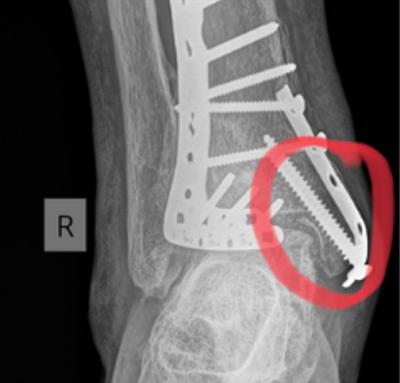

Peesscheur illustratie

Bij een volledige ruptuur kan beweging in het getroffen gebied vrijwel onmogelijk zijn. Een gedeeltelijke scheur kan minder opvallende klachten geven, maar kan alsnog leiden tot langdurige pijn en functieverlies. Bij een volledige ruptuur kan het nodig zijn dat er een operatie nodig is. Dit moet zo snel mogelijk gebeuren na de ruptuur omdat het lichaam de spier/ pees anders zelf opruimt. Een peesscheur kan worden vastgesteld door lichamelijk onderzoek, een echo of ander beeldvormend onderzoek.